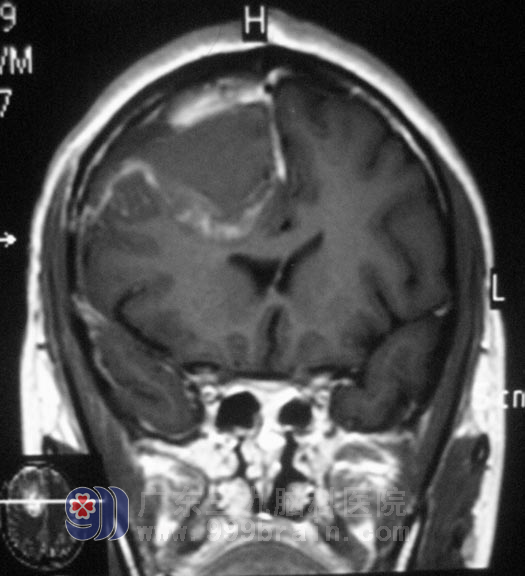

2月8日,小张在全麻下行经右侧额叶病变切除术,术中显微镜下见额叶皮层下黄白色病变,麻醉唤醒他,电生理检测测定功能区范围并标志,逐步分离切除,整个手术切除过程中小张一直保持清醒状态,并且能随时配合医生的指令动作,历时3小时后手术顺利结束。小张的脑功能保护完好,现已满意出院。术后病理结果为:肥胖型星形胶质瘤(WHO II级)。

▲手术后